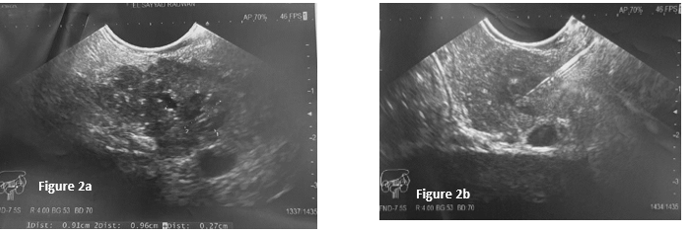

Echo endoscopic ultrasound showed a 13 mm cystic lesion obstructing the wirsung (figure 2). FNA and core biopsy was positive for a small blue cell tumor and positive for CD99. These findings were consistent of extension of Ewing sarcoma (figure 3).

Figure 2a: 13 mm cyctic lesion obstructing the wirsung which is dilated upstream.

Figure 2b: FNA needle 22G inside the lesion.